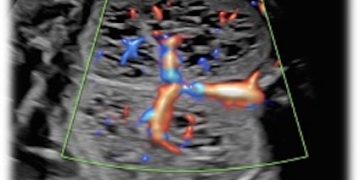

Cari soci, finalmente online le soluzioni dei casi di Maggio!!! Caso 1 Scarica il File Caso 2 [pdf-embedder url="https://www.sieog.it/wp-content/uploads/2022/05/caso-clinico-maggio-2-risposta.pdf" title="caso...